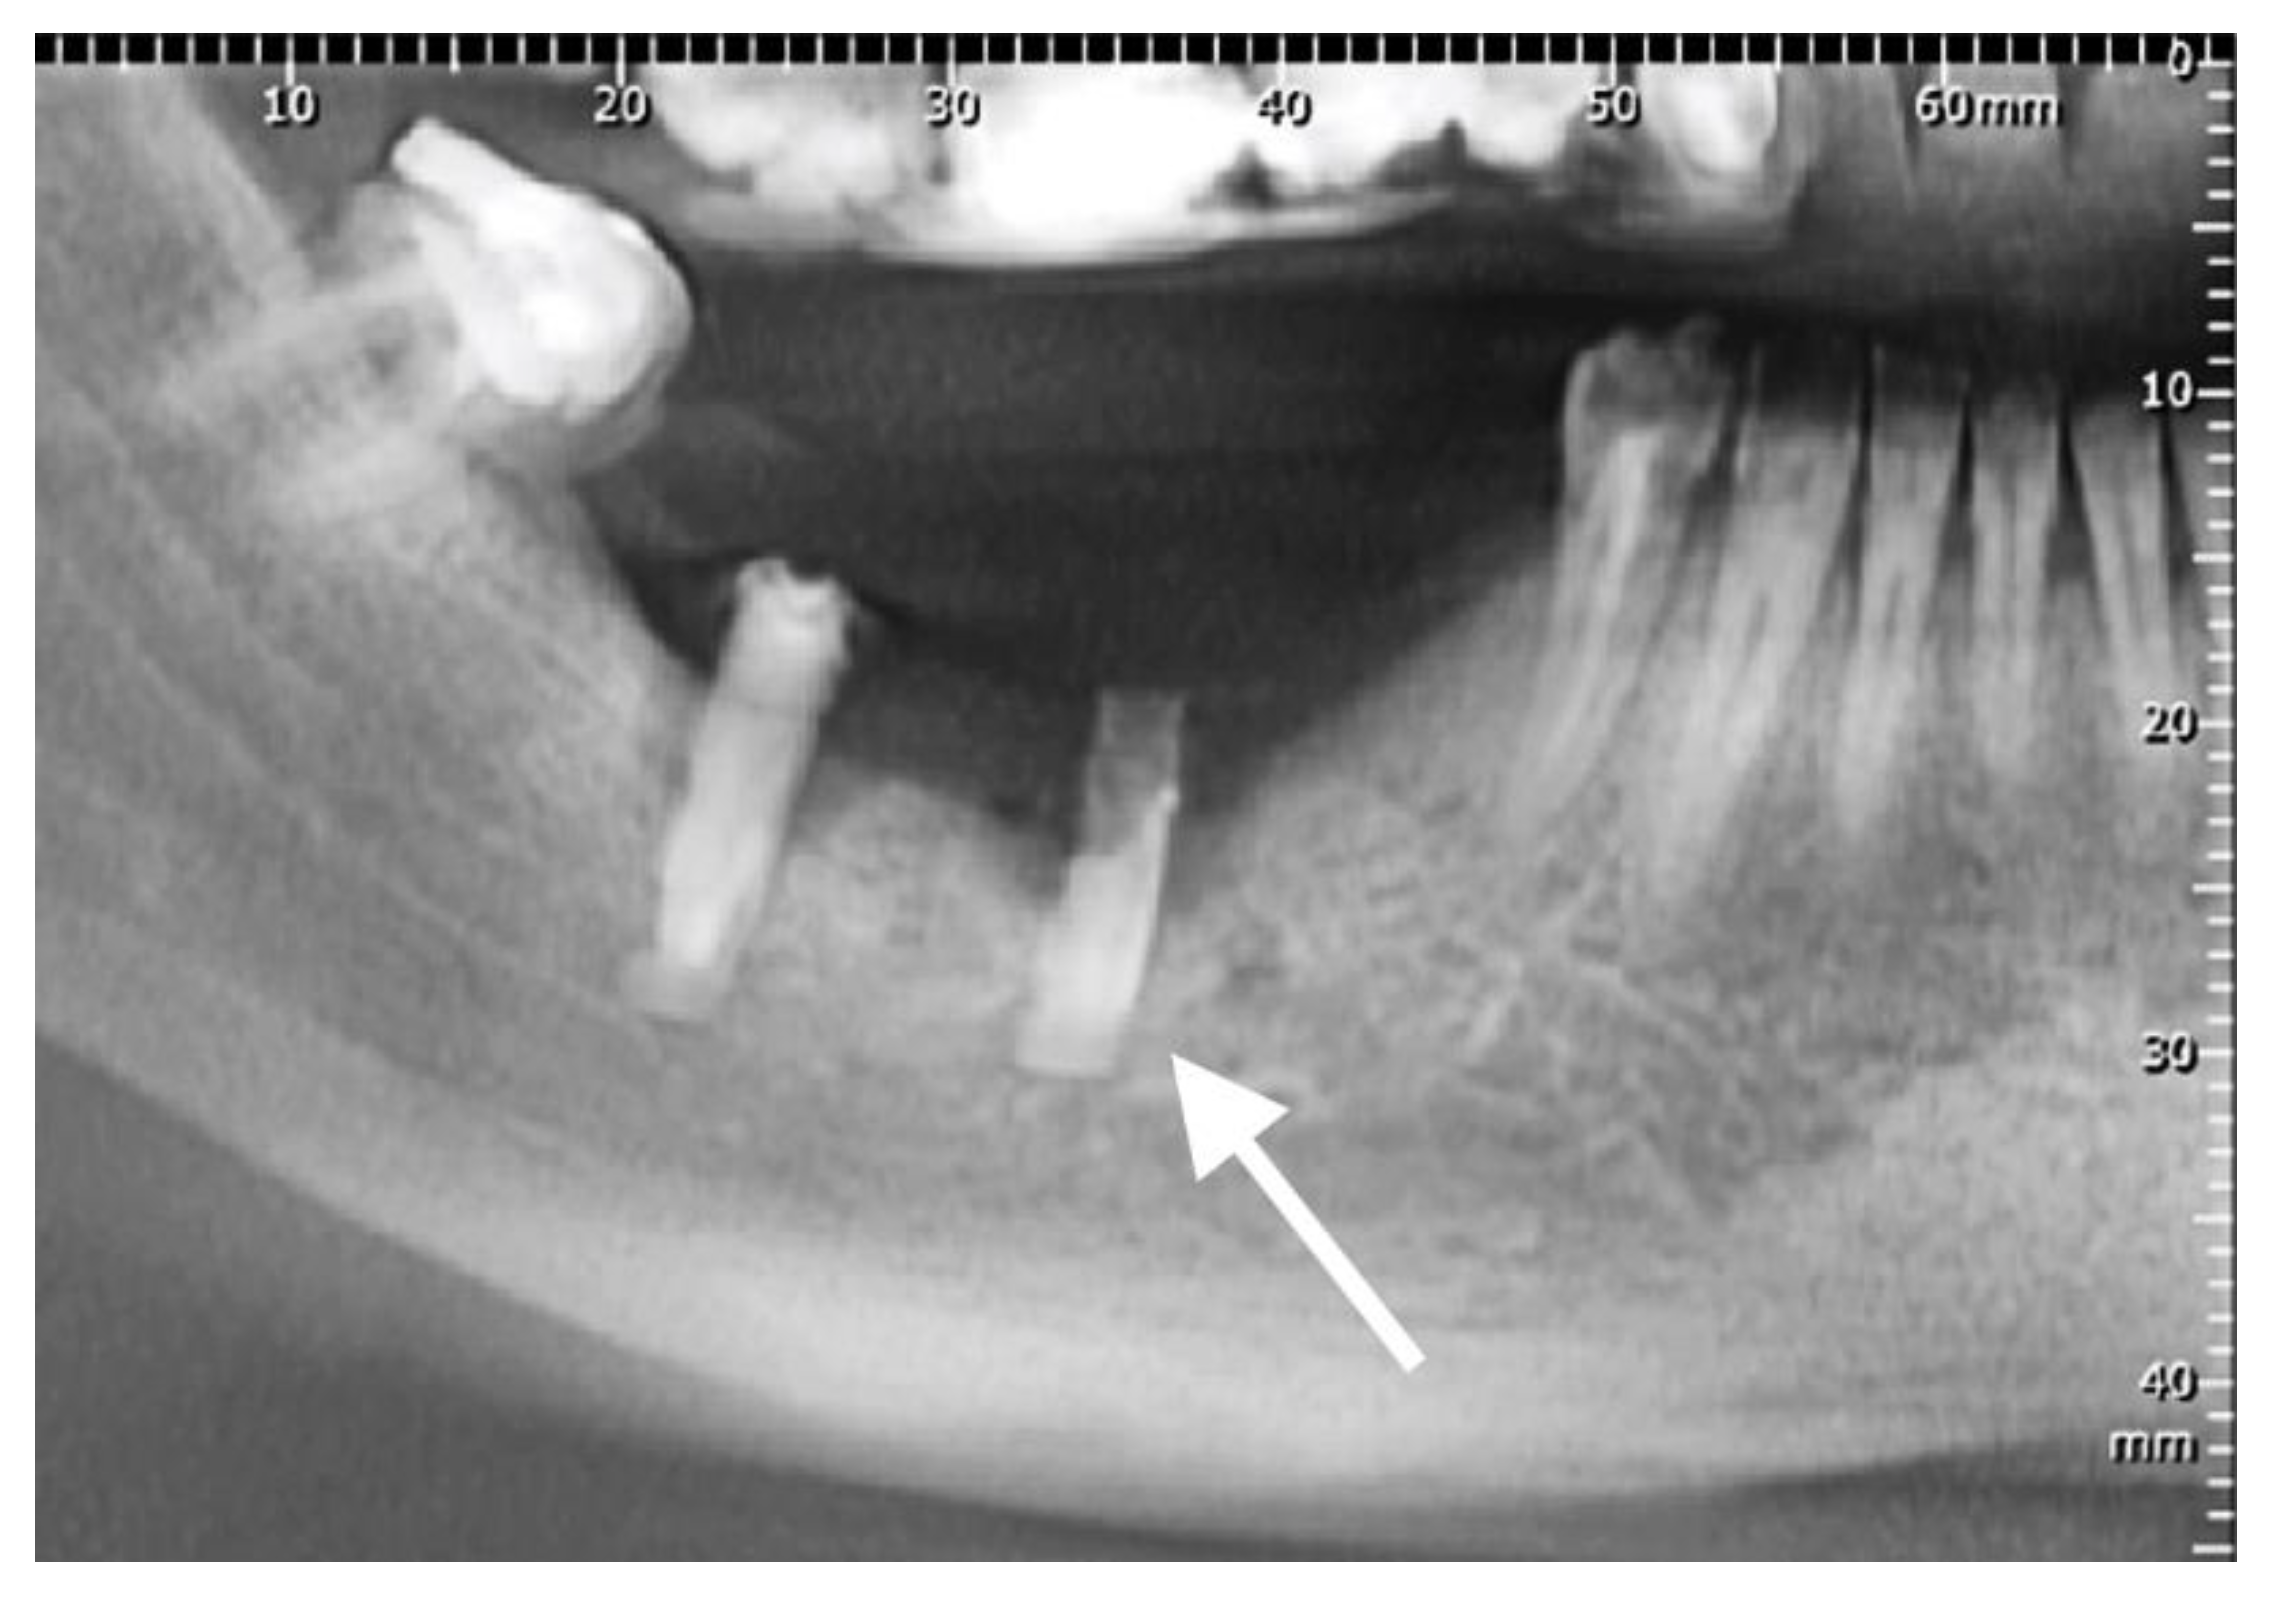

2.1. Materials

3.1. Dental Implants